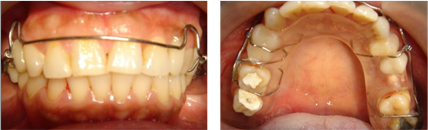

後續矯正以建立出已喪失的空間